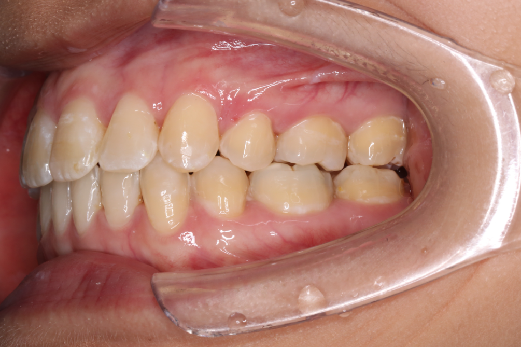

2018.11.14  术后侧面改善明显,露龈笑改善明显,笑弧笑线协调,颏部肌肉紧张度明显改善

2018.11.14  术后磨牙尖牙I类关系,中线齐,覆合,覆盖正常

Post-TXPRE-TXPost-TXNormFMIA°47°57.555.0SNA°77.7°76.883.0SNB°70.2°73.780.0ANB°7.5°3.13.0FMA° 29.828.026PFH/AFH70.5°65.970Z Angle°50.3°64.477U1-FH113.0103.7110.0 IMPA°103.291.197.0U Lip tos’ line6.3 mm3.25.0L Lip to s’ line3.9 mm1.03.0OP-FH1212.615

宏观评价:面部对称,面下三分一比例协调,上下唇凸度正常,上颌牙列内收转矩控制良好,下颌后缩改善,颏唇沟变得更加柔和,术后达到基本直面型。